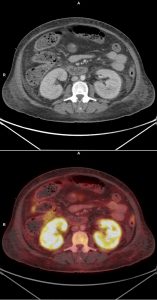

Patiente de 58 ans présentant une altération de l’état général avec fièvre et perte de poids récente.

Une TEP FDG est réalisée dans le bilan diagnostique initial.

– Fixation rénale corticale : inflammation capillaire/fuite glomérulaire du FDG (glomérulonéphrite)

– Fixation pulmonaire diffuse + sd interstitiel : hémorragie intra-alvéolaire

– Hyperfixations utérine + ADP pathologiques

– Fixations ostéo-médullaire + splénomégalie inflammatoires

Le diagnostic est bien celui de lymphome agressif (ici B diffus à grandes cellules non GC) avec dissémination intra-vasculaire et notamment atteinte ganglionnaire sus et sous diaphragmatique.

La particularité de ce cas était donc la dissémination intra-vasculaire se traduisant ici par une hyperfixation diffuse du parenchyme pulmonaire, rénal et utérin ; l’atteinte préférentielle de ces organes serait due à leur richesse en petits vaisseaux sanguins.